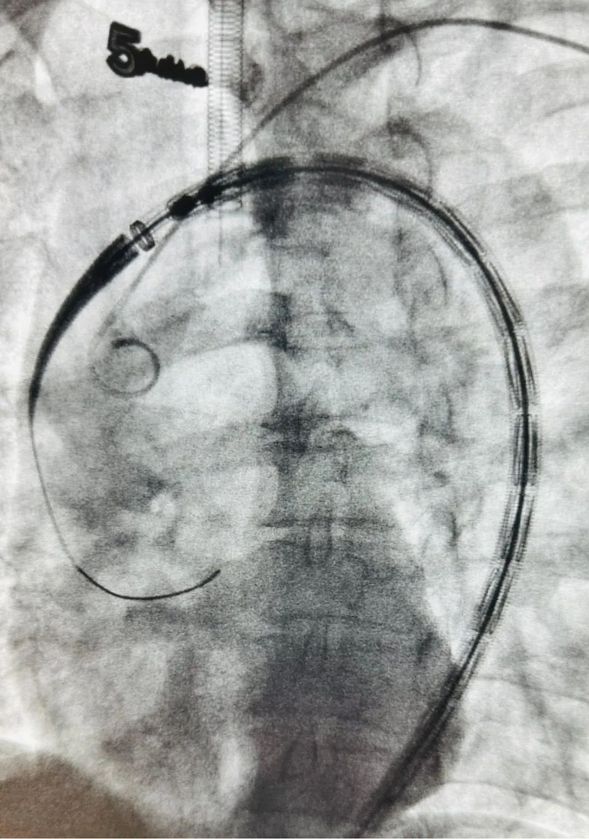

血管外科医生行胸主动脉覆膜支架置入术

术中影像